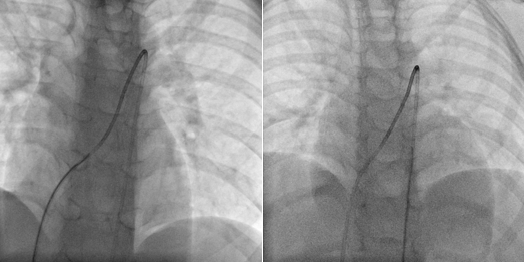

Through the femoral vein, a 5-Fr multipurpose A catheter (MP-A catheter, Cordis) was used in an attempt to cross the PDA from the MPA directly or with the assistance of a guidewire. If the antegrade approach was not successful after more than 5 minutes, operators switched to the kissing-catheter method. The antegrade catheter was left in the middle of the MPA. From the femoral artery, another 5-Fr MP-A catheter (retrograde catheter) was introduced to the descending aorta and advanced through the PDA to the middle of the MPA directly or with the assistance of a guidewire. Under a 30° cranial with 15° left anterior oblique (LAO) fluoroscopic projection, operators manipulated the antegrade and retrograde catheters simultaneously so that their distal ends would dock with each other tip to tip. A 260-cm, 0.035-inch exchange guidewire was sent from one of the catheters to another, through the docking-junction, and externalized from the proximal end of the catheter. Then, an artery-PDA-vein guidewire loop was established (Figures 1-3; Videos 1 and 2).

Over this guidewire rail, the delivery sheath was advanced from the venous side through the PDA and into the descending aorta. The device (ADO, or domestic mushroom-shaped occluder) was deployed to occlude the PDA and released after aortogram confirmed the proper position and no significant residual leak. All patients had echocardiographic follow-up at 24 hours, and 1, 3, 6, and 12 months after closure.